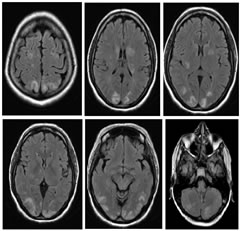

Figure 3: Posterior reversible encephalopathy syndrome (PRES) in a Primi gravida with preclampsia and twin pregnancy, presented with severe headache and seizures on first postoperative day of emergency LSCS.MRI showed holohemispheric patttern of involvement . (a,b,c,d,e) FLAIR cortical, subcortical edema in bilateral front,parietal, temporal and occipital lobes,bilateral cerebellar hemispheres,head of caudate nucleus on right side. (f,g) Area of restricted diffusion seen in the left parieto-occipital lobe.